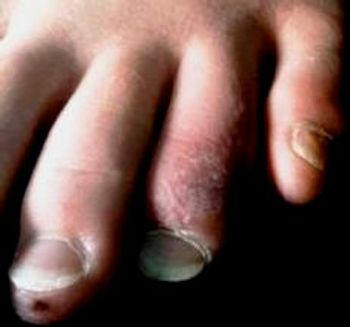

A 20-year-old woman presents in mid-winter with a mildly painful, swollen, and discolored left toe of a week’s duration. What cause do you suspect?